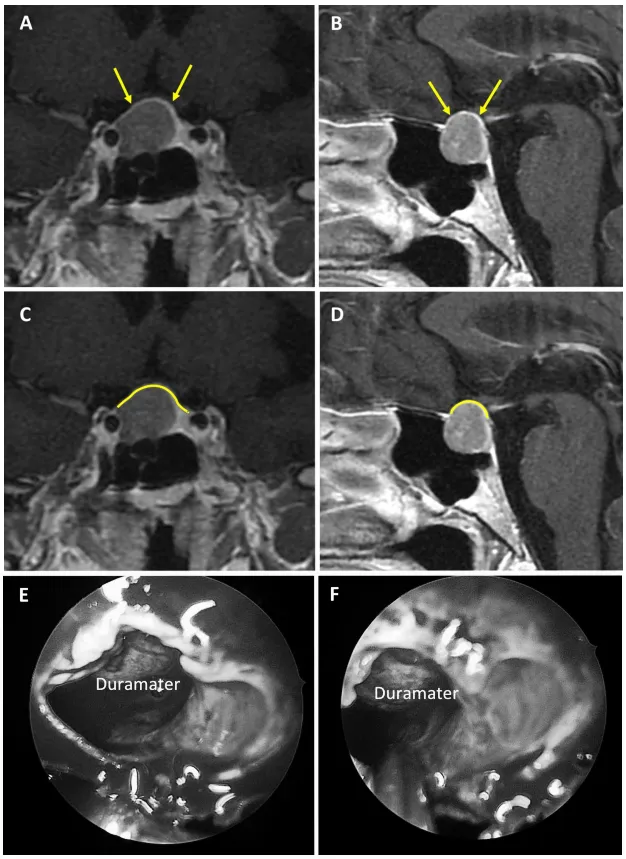

1强韧型鞍隔屏障案例

图2:75岁女性无功能大腺瘤患者。a、b术前MRI:黄色箭头指示厚度大于1毫米的强化屏障区。c、d术前MRI:黄色标记线标示强韧屏障位置。e、f术中图像:可见由垂体腺构成的屏障结构。

图3:67岁女性无功能大腺瘤患者。a、b术前MRI:黄色箭头指示厚度大于1毫米的强化屏障区。c、d术前MRI:黄色标记线标示强韧屏障位置。e、f术中图像:可见由硬脑膜构成的屏障结构。